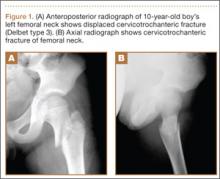

After screw removal, we recommended non-weight-bearing crutch-walking for 2 weeks followed by partial weight-bearing with crutch for another month. However, the patient started full weight-bearing 2 weeks after screw removal. One month after screw removal, he was brought to the emergency department with severe left hip pain after missing a step on a path. Anteroposterior and lateral radiographs showed an oblique subtrochanteric fracture at the empty screw holes (Figures 4A, 4B). A plate and 4 screws were placed to stabilize the subtrochanteric fracture, and a hip spica cast was applied and was to be worn for 3 weeks (Figures 5A, 5B).